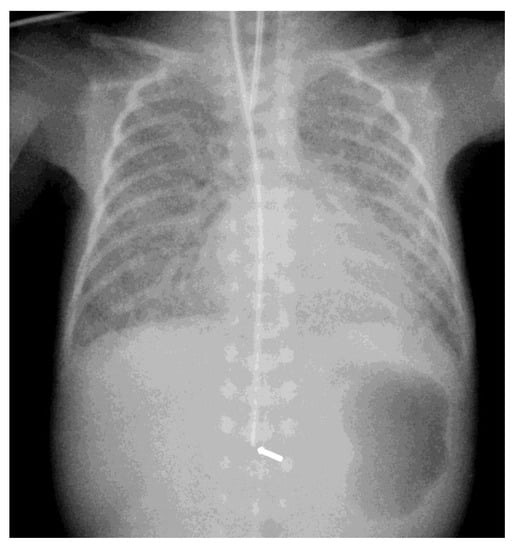

The diagnosis of EP was confirmed via the malposition of the og/ng tube in plain chest X-rays radiographic images. In infants with EP, the chest radiographic image revealed three different malpositions of the og/ng tube. In five infants, the og/ng tube was located in the right pleural cavity (pleural position) (Figure 1), which is usually connected with the pneumothorax or the pneumothorax with pleural effusion, and a radiogram of another two patients indicated mimic esophageal atresia (high position) (Figure 2). In the last three infants, the og/ng tube was located in the abdomen (low position) (Figure 3).

The pleural location of the og/ng tube is usually indicative of a sudden deterioration of the respiratory function, while the low and high position are largely asymptomatic (apart from absence of gastric contents and blood aspiration). Patients with abdominal esophageal perforations may present signs of peritonitis. Mediastinitis may develop as a result of leakage of the esophageal contents.

Radiographs of the chest are useful in demonstrating the presence of the og/ng tube in situ and might reveal three different malpositions of the nasogastric tubes, typically in the right pleural cavity associated with right-sided pneumothorax or pneumomediastinum and sometimes pleural effusion. Common symptoms in this situation are connected with the deterioration of the respiratory status. A chest radiographic image may reveal excessive amounts of air in the mediastinum. The high position of the og/ng tube mimicking an esophageal atresia effect may be due to the presence of a mass created by a false passage of air or milk in the mediastinum [9,14]. The position of the top of the og/ng tube may be helpful in differential exclusion. In true esophageal atresia, it is usually above the bifurcation of the tracheae, while in the mimic esophageal atresia, it is located below the bifurcation. In doubtful cases, esophagoscopy can be conclusive [15]. The presence of gas along the og/ng tube may also be helpful in diagnosing EP. The third possible malposition of the og/ng tube involves the intra-abdominal location, which might be associated with the absence of gas in the intestines. It must be noted that a radiographic image cross-table lateral might, in this case, indicate where the tip of the og/ng tube would appear in the posterior/retroperitoneal space. This would be advisable for a more precise diagnosis. Another complication described by Sorens was mediastinal abscess requiring chest drain insertion [16]. Occasionally, patients with intra-abdominal EP might present symptoms of peritonitis or dysphagia and drooling [1]. In our study, like Elgendys’ study, pneumothorax and septicemia were frequent complications of esophageal perforation [17]. We diagnosed peritonitis in one patient and necrotizing enterocolitis in one patient. In one patient, cardiorespiratory decompression was connected to pleural milky effusion. Chylothorax should be considered and excluded upon differential diagnosis when milk is present in the pleural cavity and milky fluid can be aspirated from the right pleural cavity. Kairamkonda linked chylothorax with esophageal perforation, which may follow when the value of the laboratory fluid analyzed shows a triglyceride level of >1.1 mmol/l with absolute cell count > 1000 cells/mcl and lymphocyte fraction > 80% [18,19,20].

Figure 3. Intra-abdominal location of the NGT. The arrow indicates the position of the nasogastric tube tip in the abdominal cavity.